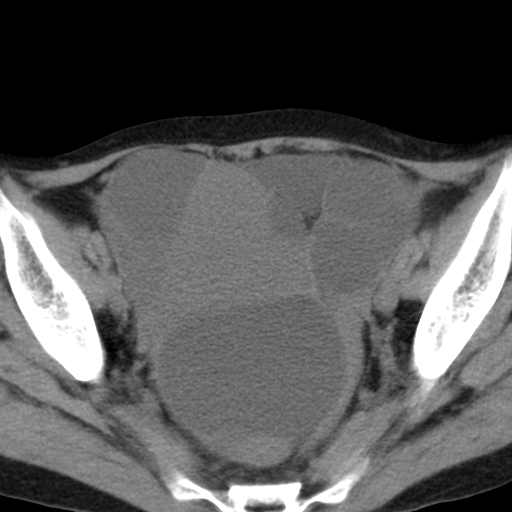

女,70,腹部间断性胀痛三月余

子宫宫腔及双侧附件积液,原因?

考虑卵巢囊腺瘤,不排除囊腺癌。

考虑卵巢囊腺瘤或囊腺癌。实质成分太多,考虑后者可能性大.

双侧卵巢粘液性囊腺癌,不多赘述。

考虑卵巢囊腺瘤;囊腺癌不能排除(理由:病人年龄较大,病灶外形欠规整、囊实相间,实性成分较多均支持囊腺癌)。要是能听听九目段老师的点评就好了!

年龄较大,囊实相间,实性成分较多均支持囊腺癌。